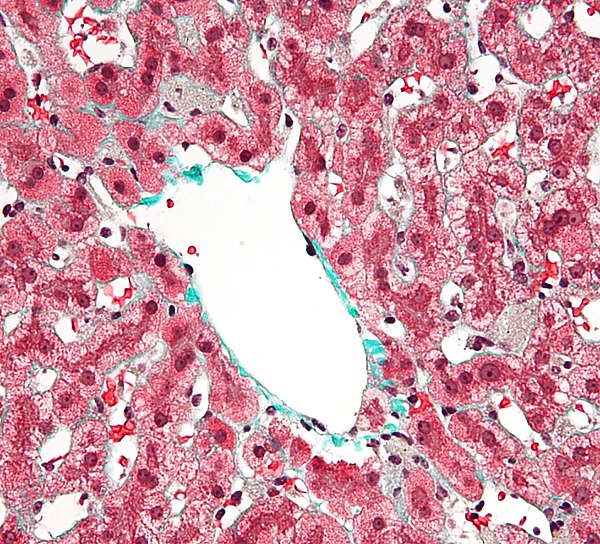

Клетки Купфера имеют амёбоидную форму и прикреплены к синусоидальным эндотелиальным клеткам. На поверхности клеток Купфера имеются микроворсинки, псевдоподии и ламеллоподии, расположенные во всех направлениях. Микроворсинки и псевдоподии задействованы в поглощении частиц. В цитоплазме клеток Купфера располагаются рибосомы, аппарат Гольджи, эндоплазматический ретикулум (в особенности, шероховатый), центриоли, микротрубочки и микрофиламенты. Ядро яйцевидное, может быть подразделено на доли. В органеллах клеток Купфера присутствует пероксидазная активность. Клетки Купфера локализованы и в центрилобулярной, и в перипортальной части долек печени, однако их функции в этих регионах различны. Перипортальные клетки Купфера более крупные, содержат больше лизосом и более активны в плане фагоцитоза, а центрилобулярные клетки Купферы специализированы на генерации супероксид-радикала. Внутри клеток Купфера имеются скэвенджер-рецепторы SR-AI/II. Они участвуют в распознавании и связывании липида A в составе молекул липополисахарида и липотейхоевых кислот. Липополисахарид является эндотоксином, входящим в состав клеточных стенок грамотрицательных бактерий, а липотейхоевые кислоты присутствуют в клеточных стенках грамположительных бактерий[4].

Среднее время жизни клеток Купфера составляет 3,8 суток. Их главная функция — удаление инородного дебриса и частиц, поступающих в печень по воротной вене. Крупные частицы, возможно, поглощаются клетками Купфера с помощью фагоцитоза, а мелкие — посредством пиноцитоза[4]. Клетки Купфера входят в систему врождённого иммунитета и играют важную роль в защите организма, а также метаболизируют различные вещества липидной природы, расщепляют белковые комплексы и мелкие частицы. Они также удаляют из кровотока апоптотические клетки. Количество клеток Купфера в печени постоянно и поддерживается с помощью апоптоза и фагоцитоза соседними клетками Купфера. Они обладают пролиферативным потенциалом и могут восстанавливать свою численность, в отличие от макрофагов, происходящих от моноцитов, которые неспособны к пролиферации. По функциям клетки Купфера гетерогенны, и клетки из разных локаций могут отличаться функционально. Например, клетки Купфера из зоны 1 дольки печени более активны, чем таковые из зоны 3, вероятно, в связи с тем, что клетки из зоны 1 больше сталкиваются с чужеродными частицами и веществами. Клетки Купфера могут продуцировать провоспалительные цитокины, в частности, фактор некроза опухоли α (TNFα) в M1-состоянии, и противовоспалительные цитокины, например, IL-10, в M2-состоянии, кислородные радикалы и протеазы. Выделение этих соединений может приводить к повреждениям печени[4]. Кроме того, клетки Купфера несут рецепторы комплемента иммуноглобулинового семейства (CRIg), и мыши, лишённые CRIg, неспособны разрушать патогенные клетки, покрытые компонентами системы комплемента. CRIg консервативны у человека и мышей и играют важную роль в работе врождённого иммунитета[7].